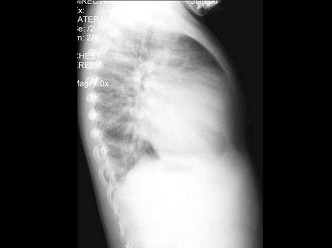

60、单项选择题

男,38岁,慢性颈痛和背痛1年余,结合图像,最可能的诊断是()

A.强直性脊柱炎

B.类风湿关节炎

C.Reiter综合征

D.关节结核

E.痛风